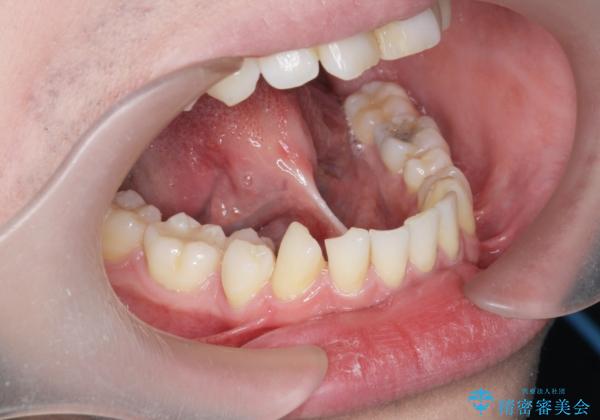

[ 舌小帯形成術 ]舌が短い 小手術での改善

- 舌が短いため動かしにくく、発音に支障があるため、舌小帯切除術を希望された方の症例です。

舌小帯の形成は10分程度で終わる小手術です。

悩みの種であった滑舌が改善できたと喜んでいただくことができました。